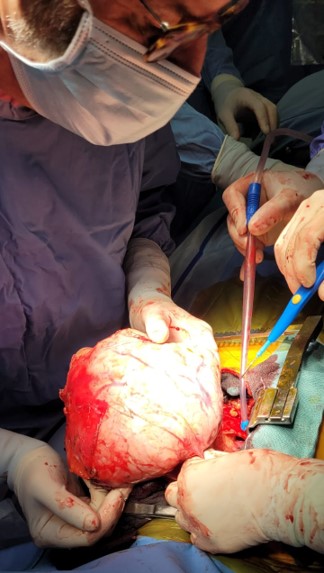

Locally advanced thymomas and thymic carcinomas

Thymomas (T) and thymic carcinomas (CT) are very rare primary neoplasms of the anterior mediastinum, with an incidence of 0.13 cases per 100,000 people/year. In most cases (and especially for T), diagnosis occurs at an early stage. They can sometimes be associated with paraneoplastic syndromes, of which myasthenia gravis (MG) is the most common.

However, in 7-11% of cases, the tumour is diagnosed in a more invasive form (especially in TC), with possible invasion of the pleura, pericardium, lung, or directly the adjacent anatomical structures (especially the great vessels). Even after radical surgery (R0), recurrence is possible in 30-35% of cases. The optimal treatment of locally advanced thymic neoplasms requires a multidisciplinary approach involving the oncologist, radiotherapist, thoracic surgeon, pulmonologist, and pathologist.

Surgery, especially radical , remains the treatment of choice even for the most aggressive and advanced tumours. In addition, patients with these types of cancer are generally younger and in better condition than those with lung or oesophageal cancer, and are therefore more able to tolerate combined chemo-radiotherapy treatments and/or more complex procedures.Patients with advanced neoplasms are generally treated with induction chemotherapy (usually 4 cycles ), followed by surgery and, if necessary, radiotherapy (in the event of invasion of adjacent structures or residual disease).

In case of locoregional recurrence, upfront surgery is often indicated, especially if it is deemed feasible with oncological radicality.In cases of locally advanced lesions and/or recurrence after previous surgery, surgery is complex, requiring the possible resection of various thoracic structures and sometimes a combined approach with other specialist surgical teams. It also requires significant involvement of anaesthetists, who are involved in the difficult pre-, intra- and post-operative management of these patients.

In the last three years, the Thoracic Surgery Unit in Baggiovara has treated a large number of patients with advanced/recurrent T or TC, sometimes in collaboration with cardiac surgeons from the Hesperia Hospital in Modena, making it one of the Italian thoracic surgery units with the most clinical experience in this field. The current clinical research project plans to further increase the number of such patients and, at the same time, to deepen collaboration with oncologists and radiotherapists in order to standardize the treatment protocol for these diseases and increase the long-term survival of these patients.